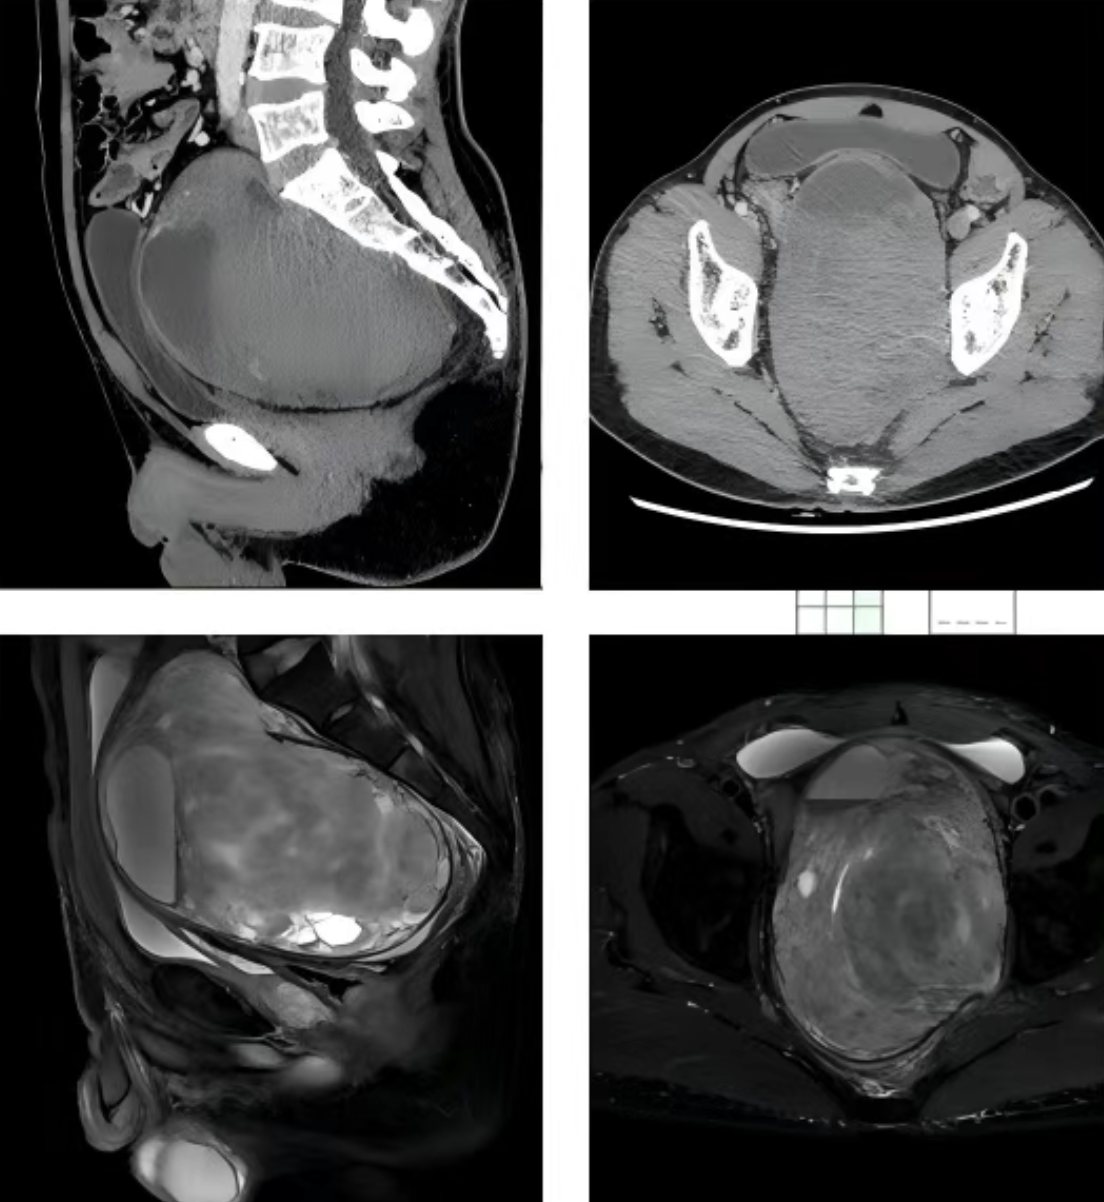

近日,潍坊市人民医院完成了一例复杂的盆腔肿瘤切除手术。在胡永成教授的指导下,脊柱退变与肿瘤科伦登兴团队联合介入放射科、泌尿外科医学中心、急诊部外科,四个科室通力协作,成功将巨大盆腔神经源性肿瘤完整切除,帮李女士卸下了身体里的“沉重包袱”。

李女士盆腔内的这个神经源性肿瘤,并非等闲之辈。它体积巨大,直径堪比一个小西瓜,如同一颗定时炸弹深藏于盆腔。随着肿瘤的不断“扩张地盘”,严重压迫到了膀胱和直肠,导致李女士频频跑厕所,夜晚难以安眠;排便也变得越来越费劲,腹部总是胀痛不适,连弯腰、久坐都成了一种负担。

更麻烦的是,它位置很深,周围都是重要的血管和脏器,手术既要将它清除,又不能伤及无辜,难度非常高。